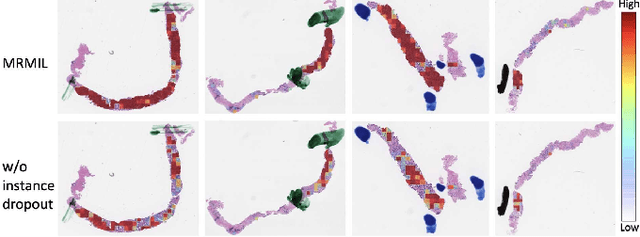

A Multi-resolution Model for Histopathology Image Classification and Localization with Multiple Instance Learning

Nov 05, 2020

Histopathological images provide rich information for disease diagnosis. Large numbers of histopathological images have been digitized into high resolution whole slide images, opening opportunities in developing computational image analysis tools to reduce pathologists' workload and potentially improve inter- and intra- observer agreement. Most previous work on whole slide image analysis has focused on classification or segmentation of small pre-selected regions-of-interest, which requires fine-grained annotation and is non-trivial to extend for large-scale whole slide analysis. In this paper, we proposed a multi-resolution multiple instance learning model that leverages saliency maps to detect suspicious regions for fine-grained grade prediction. Instead of relying on expensive region- or pixel-level annotations, our model can be trained end-to-end with only slide-level labels. The model is developed on a large-scale prostate biopsy dataset containing 20,229 slides from 830 patients. The model achieved 92.7% accuracy, 81.8% Cohen's Kappa for benign, low grade (i.e. Grade group 1) and high grade (i.e. Grade group >= 2) prediction, an area under the receiver operating characteristic curve (AUROC) of 98.2% and an average precision (AP) of 97.4% for differentiating malignant and benign slides. The model obtained an AUROC of 99.4% and an AP of 99.8% for cancer detection on an external dataset.